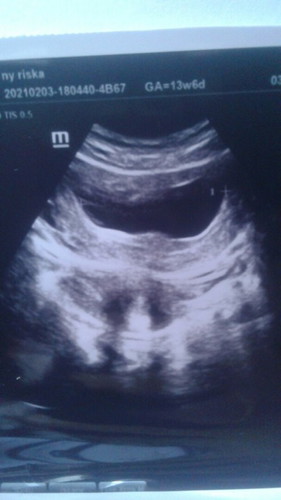

kecewa campur aduk dengan sedih karena telah dianogsa kandungan kosong .karena sudah keguguran sedih banget karena penantian begitu panjang 10 bulan dari nikah baru hamil euh pas hamil petama yang di damba2kn malah hasih nya kaya gini keguguran.sedih dan tersisak banget karena emang anak pertama dan mau banget punya bayi tapi itu semua udah di atur sama alloh karena alloh punya rencana yang begitu indah setelah ini.semoga tidak lama kemudian di kasih kepercayaan lagi sama alloh dan positif hamil lagi.amiin yarobalalaminđđ #bantusharing